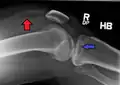

Lipohermatrosis (presencia de grasa y sangre provenientes de la médula ósea en el espacio de la articulación después de una fractura interarticular) visto con Rayos-X en una persona con una leve fractura de meseta tibial.

Lipohermatrosis debida a una fractura de meseta tibial